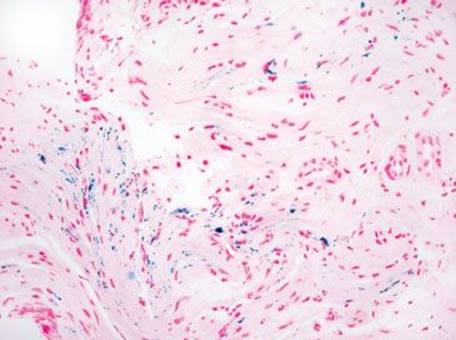

Gastric iron deposition is seen in up to 3.8% of upper tract biopsies (Fig. 2.228).23,24,183–185 In a study of 500 gastric biopsies, the deposition was demonstrated in three generalized patterns. Pattern A (also referred to as “nonspecific gastric siderosis”) was the most common subpattern and involved 2.2% of specimens (Figs. 2.229 and 2.230). This subpattern was associated with prior mucosal microhemorrhages, and the subtle depositions were predominantly identified within macrophages and stromal cells of the lamina propria. Pattern B (also referred to as “iron pill gastritis”) was seen in 0.8% of the biopsies and was consistently associated with ferrous sulfate therapy. This deposition was coarse and crystalline and predominantly identified in the extracellular and most superficial aspect of the biopsy (Figs. 2.231–2.234). In this subpattern, the background mucosa had a reactive gastritis/gastropathy pattern with erosions, ulcerations, and fibrino-inflammatory exudate common. In a separate study of 1,300 gastric biopsies, a similar “iron pill gastritis” injury pattern was detailed.184 This latter group reproduced the identical iron deposits in the laboratory by oxidizing ferrous sulfate tablets, providing clear evidence for the iron origin of these deposits. The mechanism of injury is a bit unclear in this subpattern. Some speculate that the iron pill has a direct caustic effect on the adjacent mucosa, whereas others suggest that the iron deposits may simply colonize previously injured mucosa. Pattern C (also referred to as “gastric glandular siderosis”) was the least common pattern, involving 0.6% of the specimens. This subpattern was associated with iron overload settings, such as hereditary hemochromatosis and multiple blood transfusions. The characteristic deposits were subtle, uniform, and identified in the deep antral and oxyntic glands (Figs. 2.235–2.239). The iron deposits can be highlighted blue with a Prussian blue iron special stain. Recognition is important to help prevent further injury and potential stricture formation (pattern B), to suggest pertinent iron overload evaluation (pattern C), and to avoid overdiagnosing the marked reactive epithelial change as dysplasia.

Figure 2.230 Iron pattern A/“nonspecific gastric siderosis” (Prussian Blue). The iron is blue on a Prussian Blue special stain, supporting the previously mentioned diagnosis.